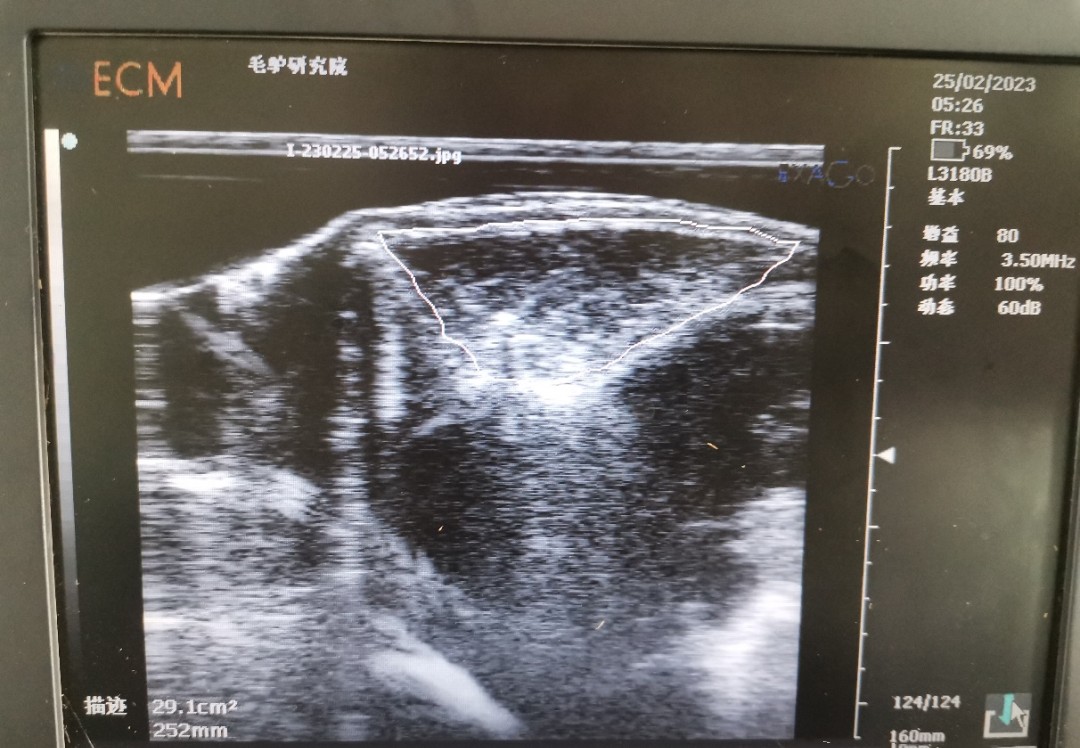

背膘活體測定可反應家畜的膘情,而家畜的膘情與繁殖性狀相關。已有研究表明,豬的背膘和眼肌面積的研究已經非常成熟,豬的背膘厚與繁殖性狀相關,眼肌面積與生產性狀相關。同時,近年來在牛上也陸續(xù)開展背膘和眼肌面積工作的測定。背膘厚度及眼肌面積的活體測定,在指導動物的生產、精準飼喂、動物的遺傳改良中發(fā)揮較好作用,使家畜育種和生產工作取得了較大進展。但此技術在驢上應用卻較少。

為了彌補背膘和眼肌面積在驢上的應用空白,我團隊開展了德州驢背膘和眼肌面積的測定工作。為更好的驗證所測定的結果,團隊成員在已屠宰的德州驢上進行確認,確保測量結果準確性。背膘厚及眼肌面積性狀在驢遺傳育種上的應用將為選育更加優(yōu)良的德州驢種質提供了新的指標,可加快驢種質創(chuàng)新步伐。